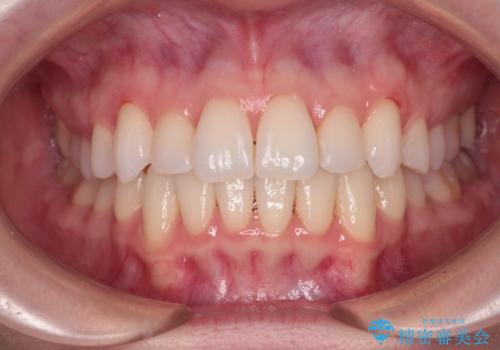

【モニター】インビザラインで気になるデコボコと八重歯をきれいに整える

- 上下前歯のデコボコ、特に右上の八重歯を気にして来院された患者様です。

妊娠、出産の予定があり、毎月の通院が困難となる可能性があったため、インビザラインによる矯正治療を行うこととしました。

事前に親知らずを抜歯しておき、出産時期に困ることのないように準備をした上で治療を開始しました。

治療後半では悪阻によりマウスピースの装着時間が不十分となることもありましたが、それよりも前にしっかりと装着時間を守って治療を進めることができたため、特に気になるところなく治療を終えることができました。